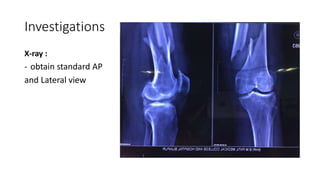

Investigations

X-ray :

- obtain standard AP

and Lateral view